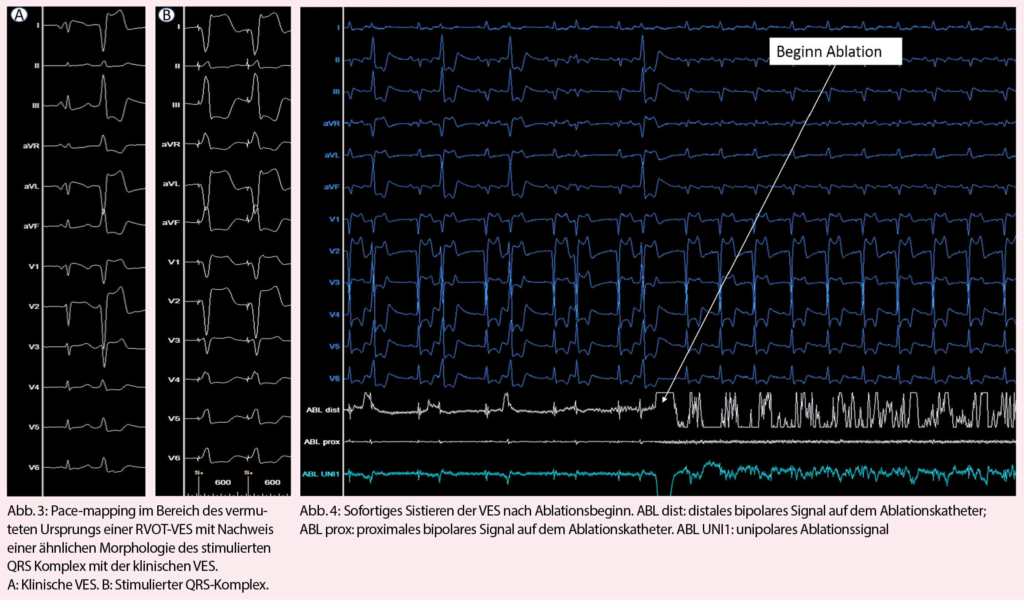

Eine Therapie-Indikation von VES besteht bei hoher Symptomlast, systolischer Herzinsuffizienz ohne eindeutig therapierbare andere Ursache, anhaltenden ventrikulären Tachykardien oder insuffizienter biventrikulärer Stimulation einer kardialen Resynchronisationstherapie. Bei asymptomatischen Patienten mit normaler LVEF und hohem VES-Burden empfiehlt sich ein expektatives Verhalten mit regelmässigen echokardiographischen Verlaufskontrollen, um die Entwicklung einer VES-assoziierten Kardiomyopathie rechtzeitig zu erkennen (41) – allerdings scheint das Intervall bis zur Abnahme der LVEF bei asymptomatischen Patienten mit gehäuften VES teilweise mehrere Jahre zu dauern und insgesamt einen sehr kleinen Anteil (geschätzte Inzidenz 5-7%) dieser Gesamtpopulation zu betreffen (36, 42). Lebensstil-Modifikationen im Sinne von reduziertem Alkohol-, Koffein- und Nikotinkonsum haben nur einen geringen Effekt auf die VES-Häufigkeit (43, 44). Ungefähr 25% der Patienten mit VES scheinen aber auf eine Kalium- oder Magnesiumsubstitution anzusprechen, wobei keine Daten bezüglich dem Effekt bei Herzinsuffizienz verfügbar sind (45). Betablocker können den VES-Burden gegenüber Plazebo signifikant senken (46), gleiches gilt für Amiodaron und Mexiletin, welche aber aufgrund des Nebenwirkungspotentials zurückhaltend eingesetzt werden (47). Klasse I Antiarrhythmika sind bei Patienten mit struktureller Herzerkrankung seit dem Nachweis einer erhöhten Mortalität von Flecainid in der CAST-Studie formal kontraindiziert, wobei das Resultat vermutlich primär durch eine heute obsolete Indikationsstellung (6VES/h = 144VES/24h) bei Patienten nach Myokardinfarkt zustande kam (48). Die elektrophysiologische Untersuchung mit RFA stellt eine interventionelle Alternative dar und muss bezüglich Eingriffsrisiko, Erfolgsaussicht und Eingriffsnutzen abgewogen werden. Die letzten zwei Jahrzehnte zeichneten sich durch enorme technische Fortschritte aus durch Entwicklung von dreidimensionalen Mapping-Verfahren mit Integration von Activation- und Pace-Mapping (Abb. 2, 3) und neue Erkenntnisse über den Effekt der RFA auf die langfristige Symptomlast, Morbidität und Mortalität. Entsprechend ist die Radiofrequenztherapie gemäss den aktuellen Leitlinien der europäischen Gesellschaft für Kardiologie eine Klasse I Indikation für die Behandlung von VES aus dem RVOT (49). Ernsthafte Komplikationen sind mit < 1% selten (39, 50). Gegenüber der pharmakologischen Therapie ist eine Ablationstherapie deutlich effizienter und anhaltender (Abb. 3) (51, 52). Der Erfolg einer RFA reicht von > 90% bei monomorphem Auftreten und Lokalisation im RVOT bis circa 60% bei Polymorphie, epikardialer oder Papillarmuskel-Lokalisation (39). Grundsätzlich ist eine RFA im Ausflusstrakt gegenüber anderen Lokalisationen mit einer grösseren Erfolgsaussicht verbunden, und ein Ursprung aus dem RVOT mit der besten Erfolgsaussicht überhaupt (Abb. 4) (53).